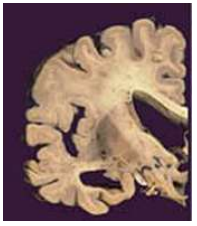

A Demência é um grave prejuízo na memória, julgamento, orientação e cognição. A figura abaixo apresenta que tipo de demência:

Assinale a alternativa CORRETA: